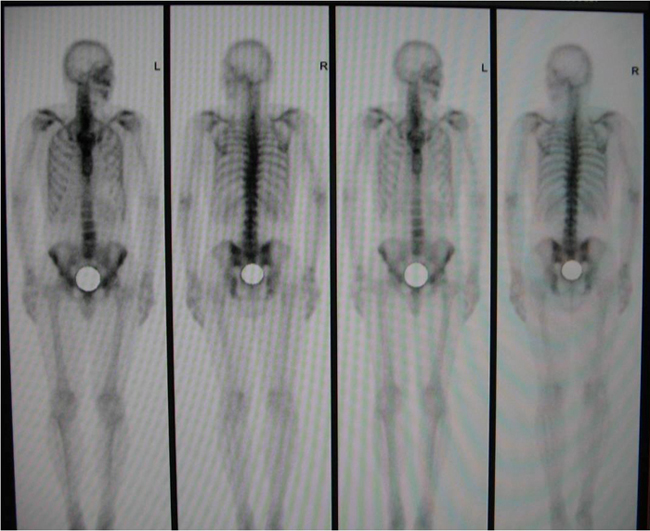

ՀՀ ԱՆ Ուռուցքաբանության ազգային կենտրոնի միջուկային բժշկության բաժանմունքը, որի ղեկավարն է պրոֆեսոր Ս.Կ. Քարամյանը, գործում է 2011 թվականից: Բաժանմունքը համալրված է «Մեդիսո» ընկերության 2 ալիքափոխ (детектор) գամմա-կամերայով, ինչը հնարավորություն է տալիս ստանալ մարդու օրգան-համակարգի մեջ ինդիկատորի տեղաբաշխման շերտավոր նկար` եռաշերտ (3D) պատկերի հետագա վերականգնմամբ (трехмерное изображение):

Այս մեթոդը հնարավորություն է ընձեռում հիվանդի վրա նվազագույն ճառագայթային ծանրաբեռնվածության պայմաններում ախտորոշել օրգան-համակարգերի ախտահարումը վաղ փուլերում: Նման հետազոտություններ Հայաստանում կատարում են եզակի կենտրոններում, իսկ, հաշվի առնելով որոշ առանձնահատկություններ, Ուռուցքաբանության ազգային կենտրոնի այս սարքը ամենաժամանակակիցն է Հայաստանում: Այս բաժանմունքում հիմնականում կատարվում են ոսկրային համակարգի, երիկամների, վահանաձև գեղձի հետազոտություններ (սցինտիգրաֆիա):